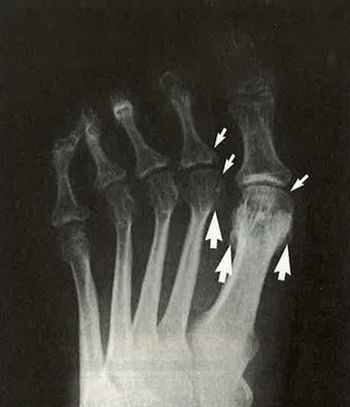

New research clarifies the presentation and treatment of nail psoriasis for rheumatologists, dermatologists and general practitioners.

The first level in management of nail psoriasis is patient education.